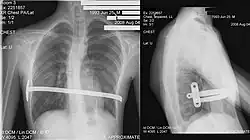

![]() X-Ray of a 15-year-old male after undergoing the procedure | |

Through two small incisions in the side of the chest, an introducer is pushed along posterior to the sternum and ribs, and anterior to the heart and lungs. Then a concave stainless steel bar is slipped under the sternum, through the incisions in the side of the chest. A third, smaller incision is made to insert a thoracoscope (small camera) used to help guide the bar. Taller patients, older patients, or patients requiring extensive correction may receive two or more bars. All bars may be placed through two incisions or additional incisions may be made. The bar is then flipped, and the sternum pops out. To support the bar and keep it in place, a metal plate called a stabilizer may be inserted with the bar on one side of the torso. PDS sutures may also be used in addition to the stabilizer. The stabilizer fits around the bar and into the ribcage. The bar and stabilizer are secured with sutures that dissolve in about six months.

Bar removal

After a period of two to four years,[6]: 343 the surgical stainless steel bar is removed from the patient's chest. This procedure lasts approximately ninety minutes. The length of time that the patient stays at the hospital following the bar removal procedure varies, depending on the amount of new bone growth surrounding the bar. Accordingly, the length of time may range from a few hours to several days, or up to one week.